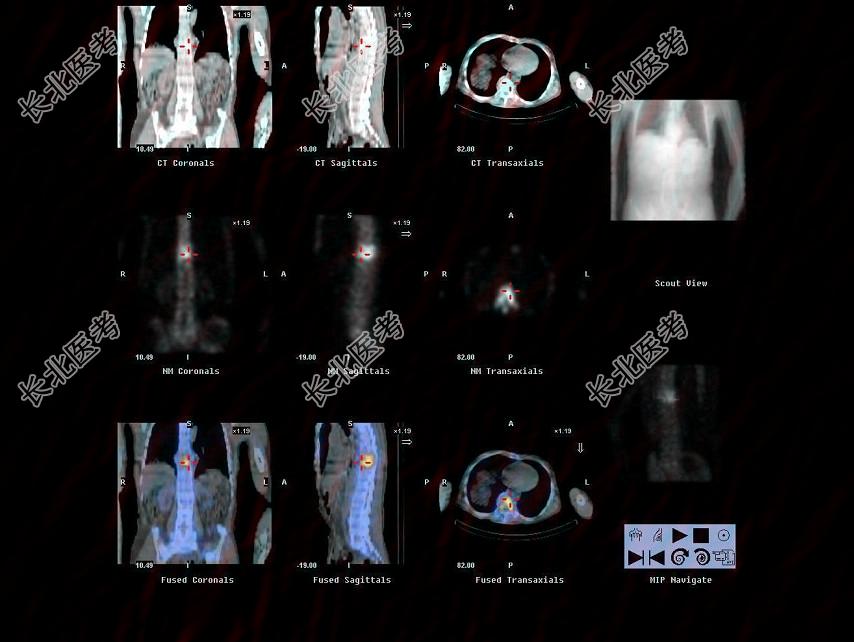

- 多项选择题男,68岁, 胸背痛3个月入院,行

Tcm-MDP全身骨显像、局部断层骨显像+X线图像融合如图, 可能的诊断是 ( )

A、胸9、10椎体良性压缩性骨折

B、大致正常的骨影像

C、胸9、10椎弓根受累,提示恶性病变

D、多发性骨髓瘤

E、胸9、10骨转移可能性大